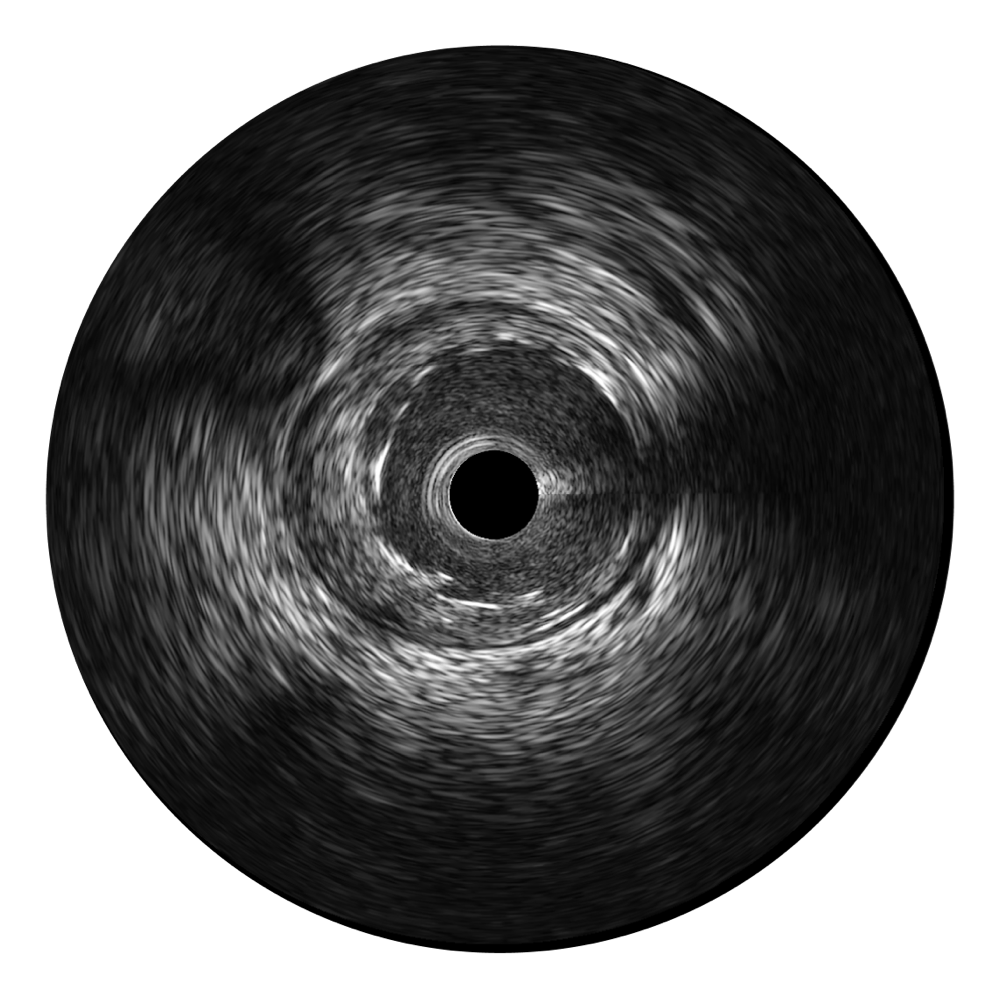

• milan米兰宽频IVUS图像

对比传统IVUS导管成像,milan米兰宽频IVUS图像的近场支架梁显影更细腻,远场中膜外血管仍清晰可辨,兼顾远中近,兼顾分辨力与穿透深度

临床图

远场分支血管及导丝

支架内血栓

组织脱垂